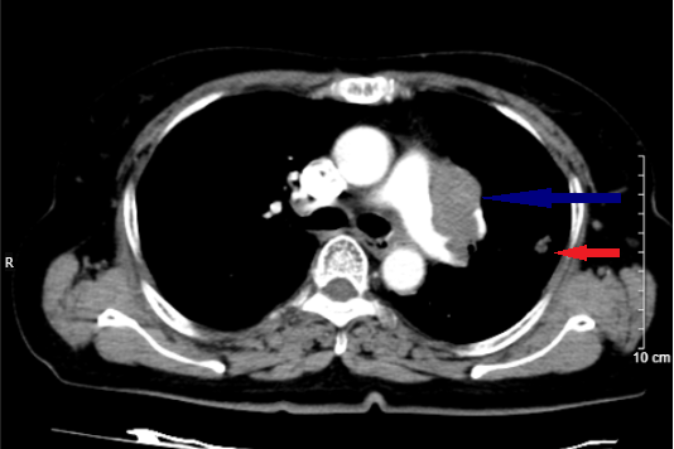

Bệnh nhân đi khám chụp X-quang tình cờ phát hiện khối u ở phổi trái nên được chuyển đến Bệnh viện Bạch Mai để khám, chẩn đoán và điều trị. Tại đây, bác sĩ chỉ định sinh thiết xuyên thành ngực khối u phổi dưới hướng dẫn chụp cắt lớp vi tính, kết quả mô bệnh học và hóa mô miễn dịch cho thấy bà bị ung thư biểu mô tế bào nhỏ.